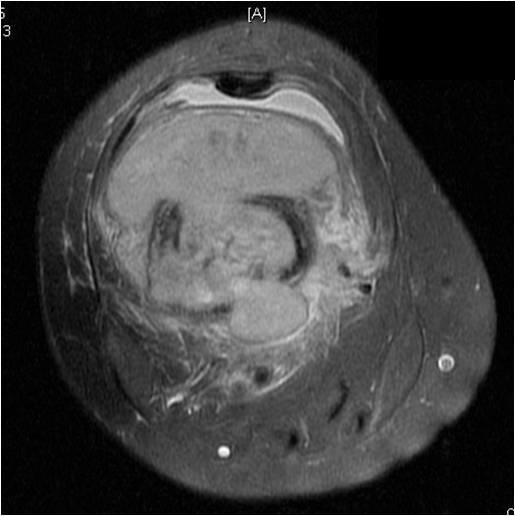

On radiographs, most MFHs of Bone are located in the metaphysis and present as purely osteolytic permeative lesions without a periosteal reaction and without mineralization (Fig. 1 &2). On MR images, MFH of Bone has ill-defined margins usually with cortical destruction of bone and extension into the soft tissues. It is usually hypo- or isointense to muscle on T1-weighted images (Fig. 3) and heterogeneous high intensity on T2-weighted images (Fig. 4-6).

Fig. 4

Fig. 4-6: MRI Axial (Fig. 4) and (Fig. 5) T2 –weighted fat-suppressed images show a heterogeneous lesion in the distal femur. Axial T2- weighted fat suppress image (Fig. 6) demonstrates a heterogeneous lesion with hyperintense areas admixed with hypointense signal areas concordant with hemorrhage and necrosis. High grade sarcomas are commonly associated with hemorrhage and necrosis.